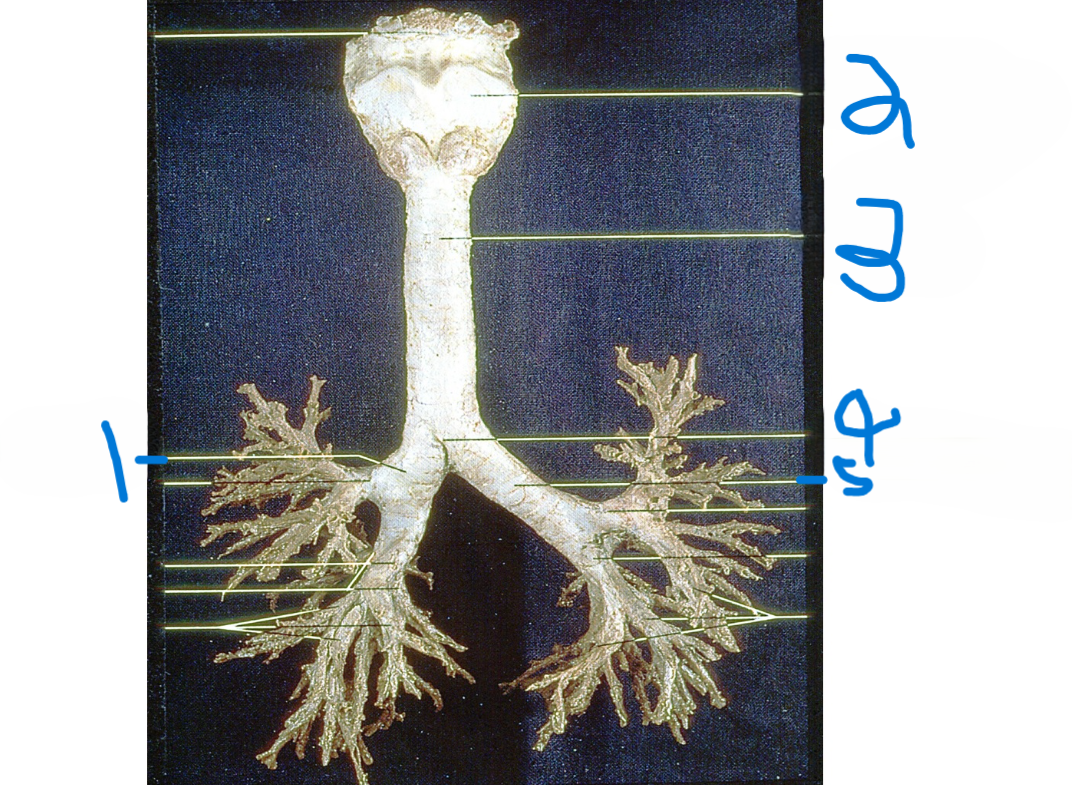

Right main bronchus

What is depicted by #1

Thyroid cartilage

What is depicted by #2

Trachea

What is depicted by #3

Carina

What is depicted by #4

Left main bronchus

What is depicted by #5